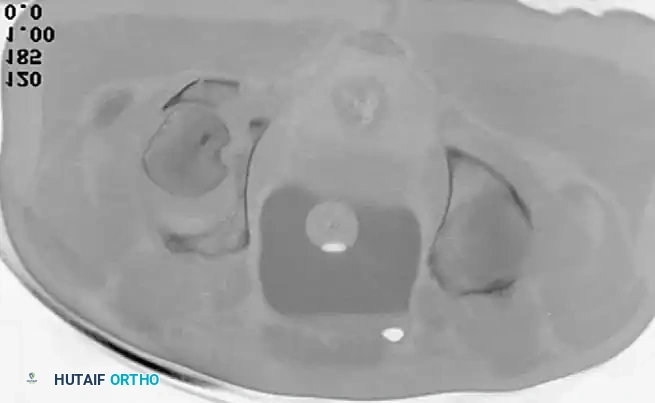

Advanced Imaging: Computed Tomography (CT)

While plain radiographs provide the foundation for classification, fine-cut CT scanning with 2D multiplanar and 3D surface-rendered reconstructions is the gold standard for modern surgical planning.

CT imaging excels at identifying:

* Intra-articular osteochondral fragments (loose bodies).

* Marginal impaction of the articular cartilage.

* The exact size and comminution of posterior wall fragments.

* The orientation of fracture lines to plan optimal screw trajectories.